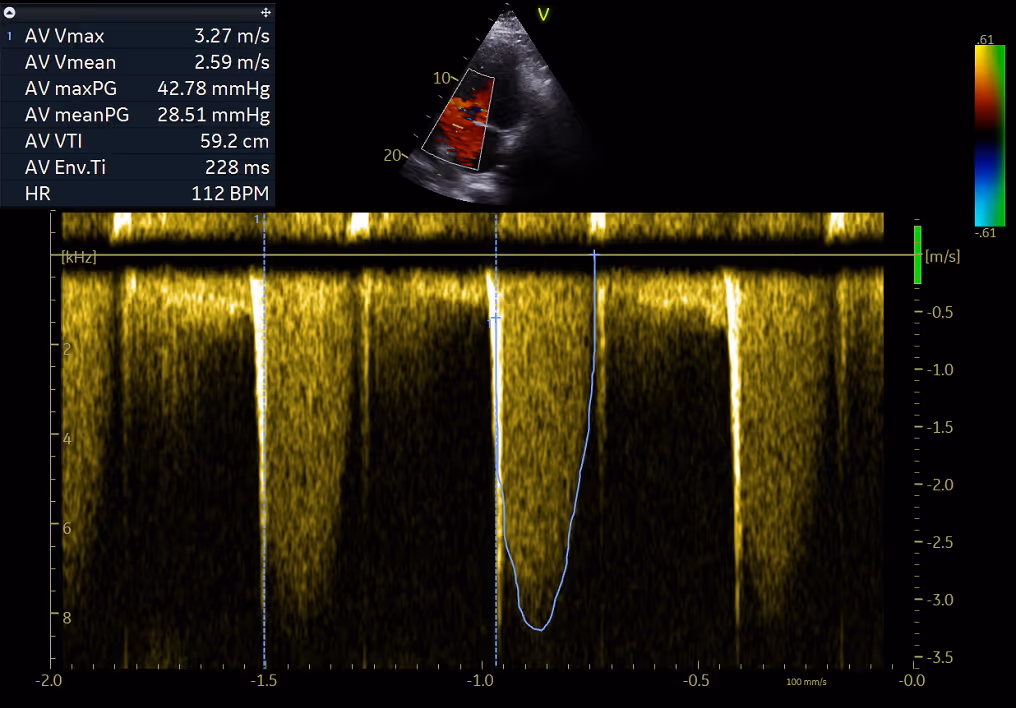

Echocardiography on admission documented a dilated left ventricle (EF 45-50%), aortic regurgitation ¾, moderate aortic stenosis (gradient 43/29 mmHg), masses on aortic valve (Image 2-3, Video 1-3).

Image 3: Moderate aortic stenosis with a maxPG: 43 mmHg